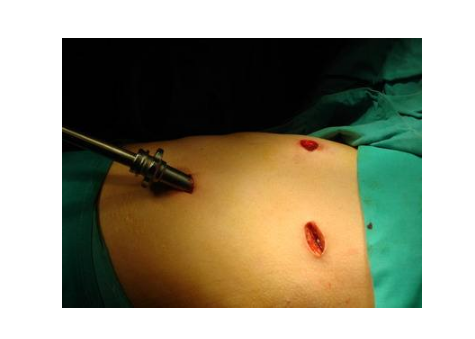

漏斗胸圖片

漏斗胸的